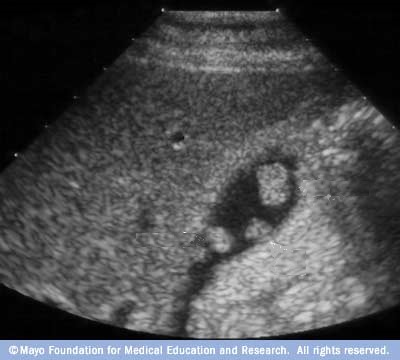

Adenome pedicule

de forme tubulaire . Aspect de adenomeme est

isoechogenique colletant au paroi par une pedicule .

Image echographique en coupe longitudinale de la

vesicule biliaire |